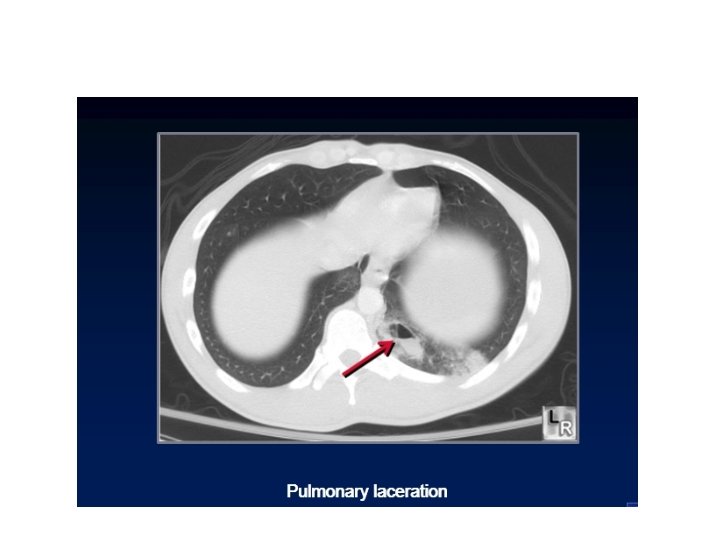

laceration • More serious condition. . With penetrating trauma. stab wound. . there is

laceration • More serious condition. . With penetrating trauma. stab wound. . there is macro scopical lung disruption with the lung torn or cut. . It can cause air to leak out of the lacerated lung in to the pleural space.

Pneumo thorax due to pulmonary laceration

Pulmonary contusion may mask pulmonary laceration on plain chest film. . Associated flail chest

Pulmonary contusion may mask pulmonary laceration on plain chest film. . Associated flail chest and sub cut. Emphysema